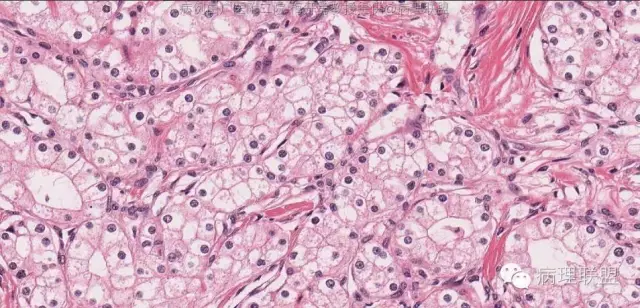

瘤细胞呈立方形,胞浆透明,核染色质粗,见小仁。未见核分裂。细胞边界清楚。

肿瘤细胞排列成腺管状或腺泡状,腺管或腺泡排列紧密,背靠背。瘤细胞形态与浆液性囊腺瘤的瘤细胞形态完全一致。因此,诊断为浆液性囊腺瘤,实体型。